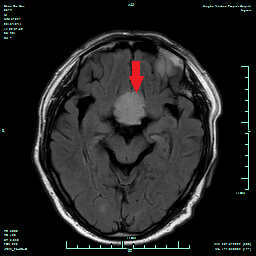

术前MRI增强,红剪头提示肿瘤大小及位置

图片1.png